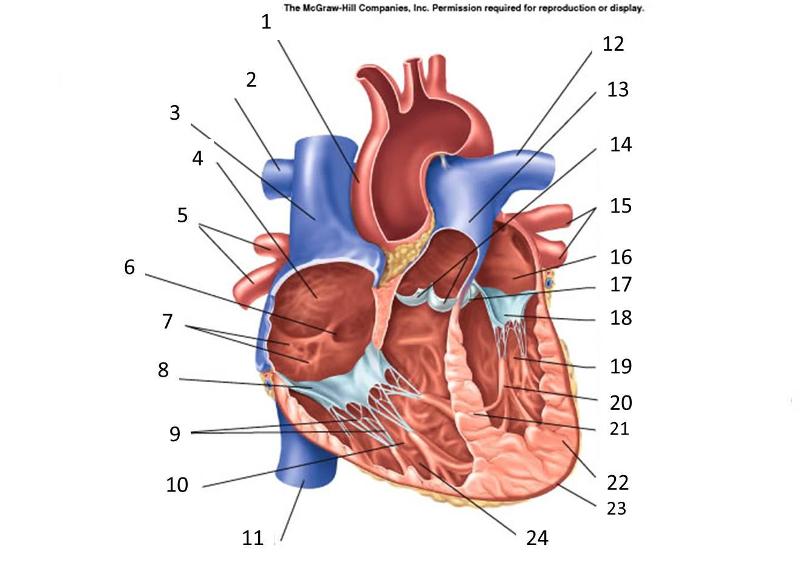

Anterior interventricular valve

Anterior interventricular sulcus

Posterior interventricular sulcus

Aortic Valve (=left semilunar)

Apex (of the heart)

Chordae tendineae

Coronary sinus

Endocardium

Epicardium

Left atrioventricular (=bicuspid, =mitral) valve

Left/right atrium

Left/right auricle

Left/right coronary artery

left/right ventricle

Myocardium

Papillary muscles

Pectinate muscles

Pericardial sac (=fibrous pericardium)

Pulmonary trunk

Pulmonary valve (=right semilunar)

Right atrioventricular (=tricuspid) valve

Superior/inferior vena cava